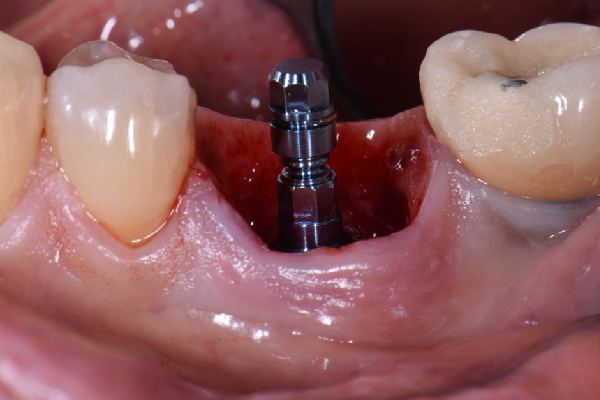

ایمپلنت دیجیتال روشی بسیاری جدی و نوین برای جایگزینی دندان و کاشت ایمپلنت است و مزیت های بسیاری نسبت به کاشت ایمپلنت معمولی دندان دارد. در این روش دندانپزشک به صورت کامل در کوتاه ترین زمان ممکن ایمپلنت دیجیتالی و پروتز دندان را با بالاترین کیفیت توسط داده های کامپیوتری که از اسکن دهان و فک شما گرفته می شود طراحی میکند و این طراحی باعث می شود تا محل دقیق کاشت دندان شما مشخص شود.

ایمپلنت دیجیتال دقت بسیار بالایی دارد و برای افرادی که تعداد ایمپلنت دندان بالایی دارند، به صورت بسیار آسان و دقیق عمل میکند و نتیجه ای فوق العاده طبیعی و شبیه به دندان های اصلی می دهد. این روش دارای ظرافت و زیبایی بوده و کمترین میزان درد را در میان سایر کاشت های ایمپلنت دیجیتال دارد. اگر شما نیز ساکن تهران هستید و به دنبال مرکز ایمپلنت دیجیتال در تهران هستید ادامه این مطلب را از دست ندهید.

همانطور که اشاره کردیم، معمولا برای پر کردن ناحیه بی دندانی یا جایگزین کردن دندان از دست رفته، به جز پروتزهای متحرک یا به وسیله بریج (روکش های متصل به هم) استفاده می شود و یا از کاشت دندان یا ایمپلنت استفاده می گردد. ایمپلنت به روش پانچ نوعی جراحی ساده کاشت دندان میباشد با کمترین درد و خونریزی انجام می شود.این روش برای افرادی کاربردی است که دارای بافت نرم در لثه و بافت محکم در استخوان داشته باشند. ایمپلنت دیجیتال دارای ظرافت و درصد خطایی پایین تری است و رضایت بیماران بیشتری دارد. در معرفی مراکز ایمپلنت دیجیتال در تهران، لیست کامل را برای شما قرار خواهیم داد. هم چنین برای مشاهده بهترین پزشکان برای ایمپلنت در شمال تهران می تواند به صفحه مربوطه مراجعه نمایید.

قیمت ایمپلنت دیجیتال در تهران سال 1401

همانطور که اشاره کردیم، ایمپلنت دیجیتال یک راه و روش نوین و بسیاری پیشرفته در حوزه دندانپزشکی مدرت است. در این روش به کسانی که دندان خود را از دست دادند این امکان را می دهد که بدون ریشه، بیمار دندان کاشت شده داشته باشد. گستردگی و سرعت بالای ایمپلنت دیجیتال باعث شده است تا قیمت بیشتری نسبت به سایر روش ها داشته باشد. با استفاده از این مدل از کاشت دندان، ظریف ترین و بدون درد ترین راه برای ایمپلنت را تجریه خواهید کرد. مزیت های ویژه این روش باعث می شود تا ارزش هزینه بیشتر نسبت به سایر مدل های کاشت دندان را داشته باشد.